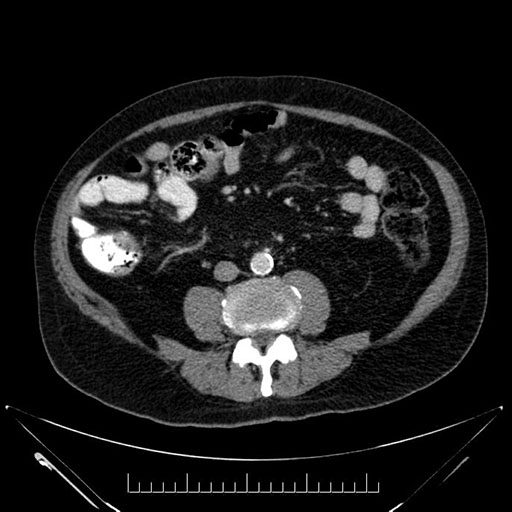

Whipple (pancreaticoduodenectomy) [case 7]

Imaging Analysis

Look through the patient's CT scan to identify any areas of concern for the necessary procedure.

Axial - stented